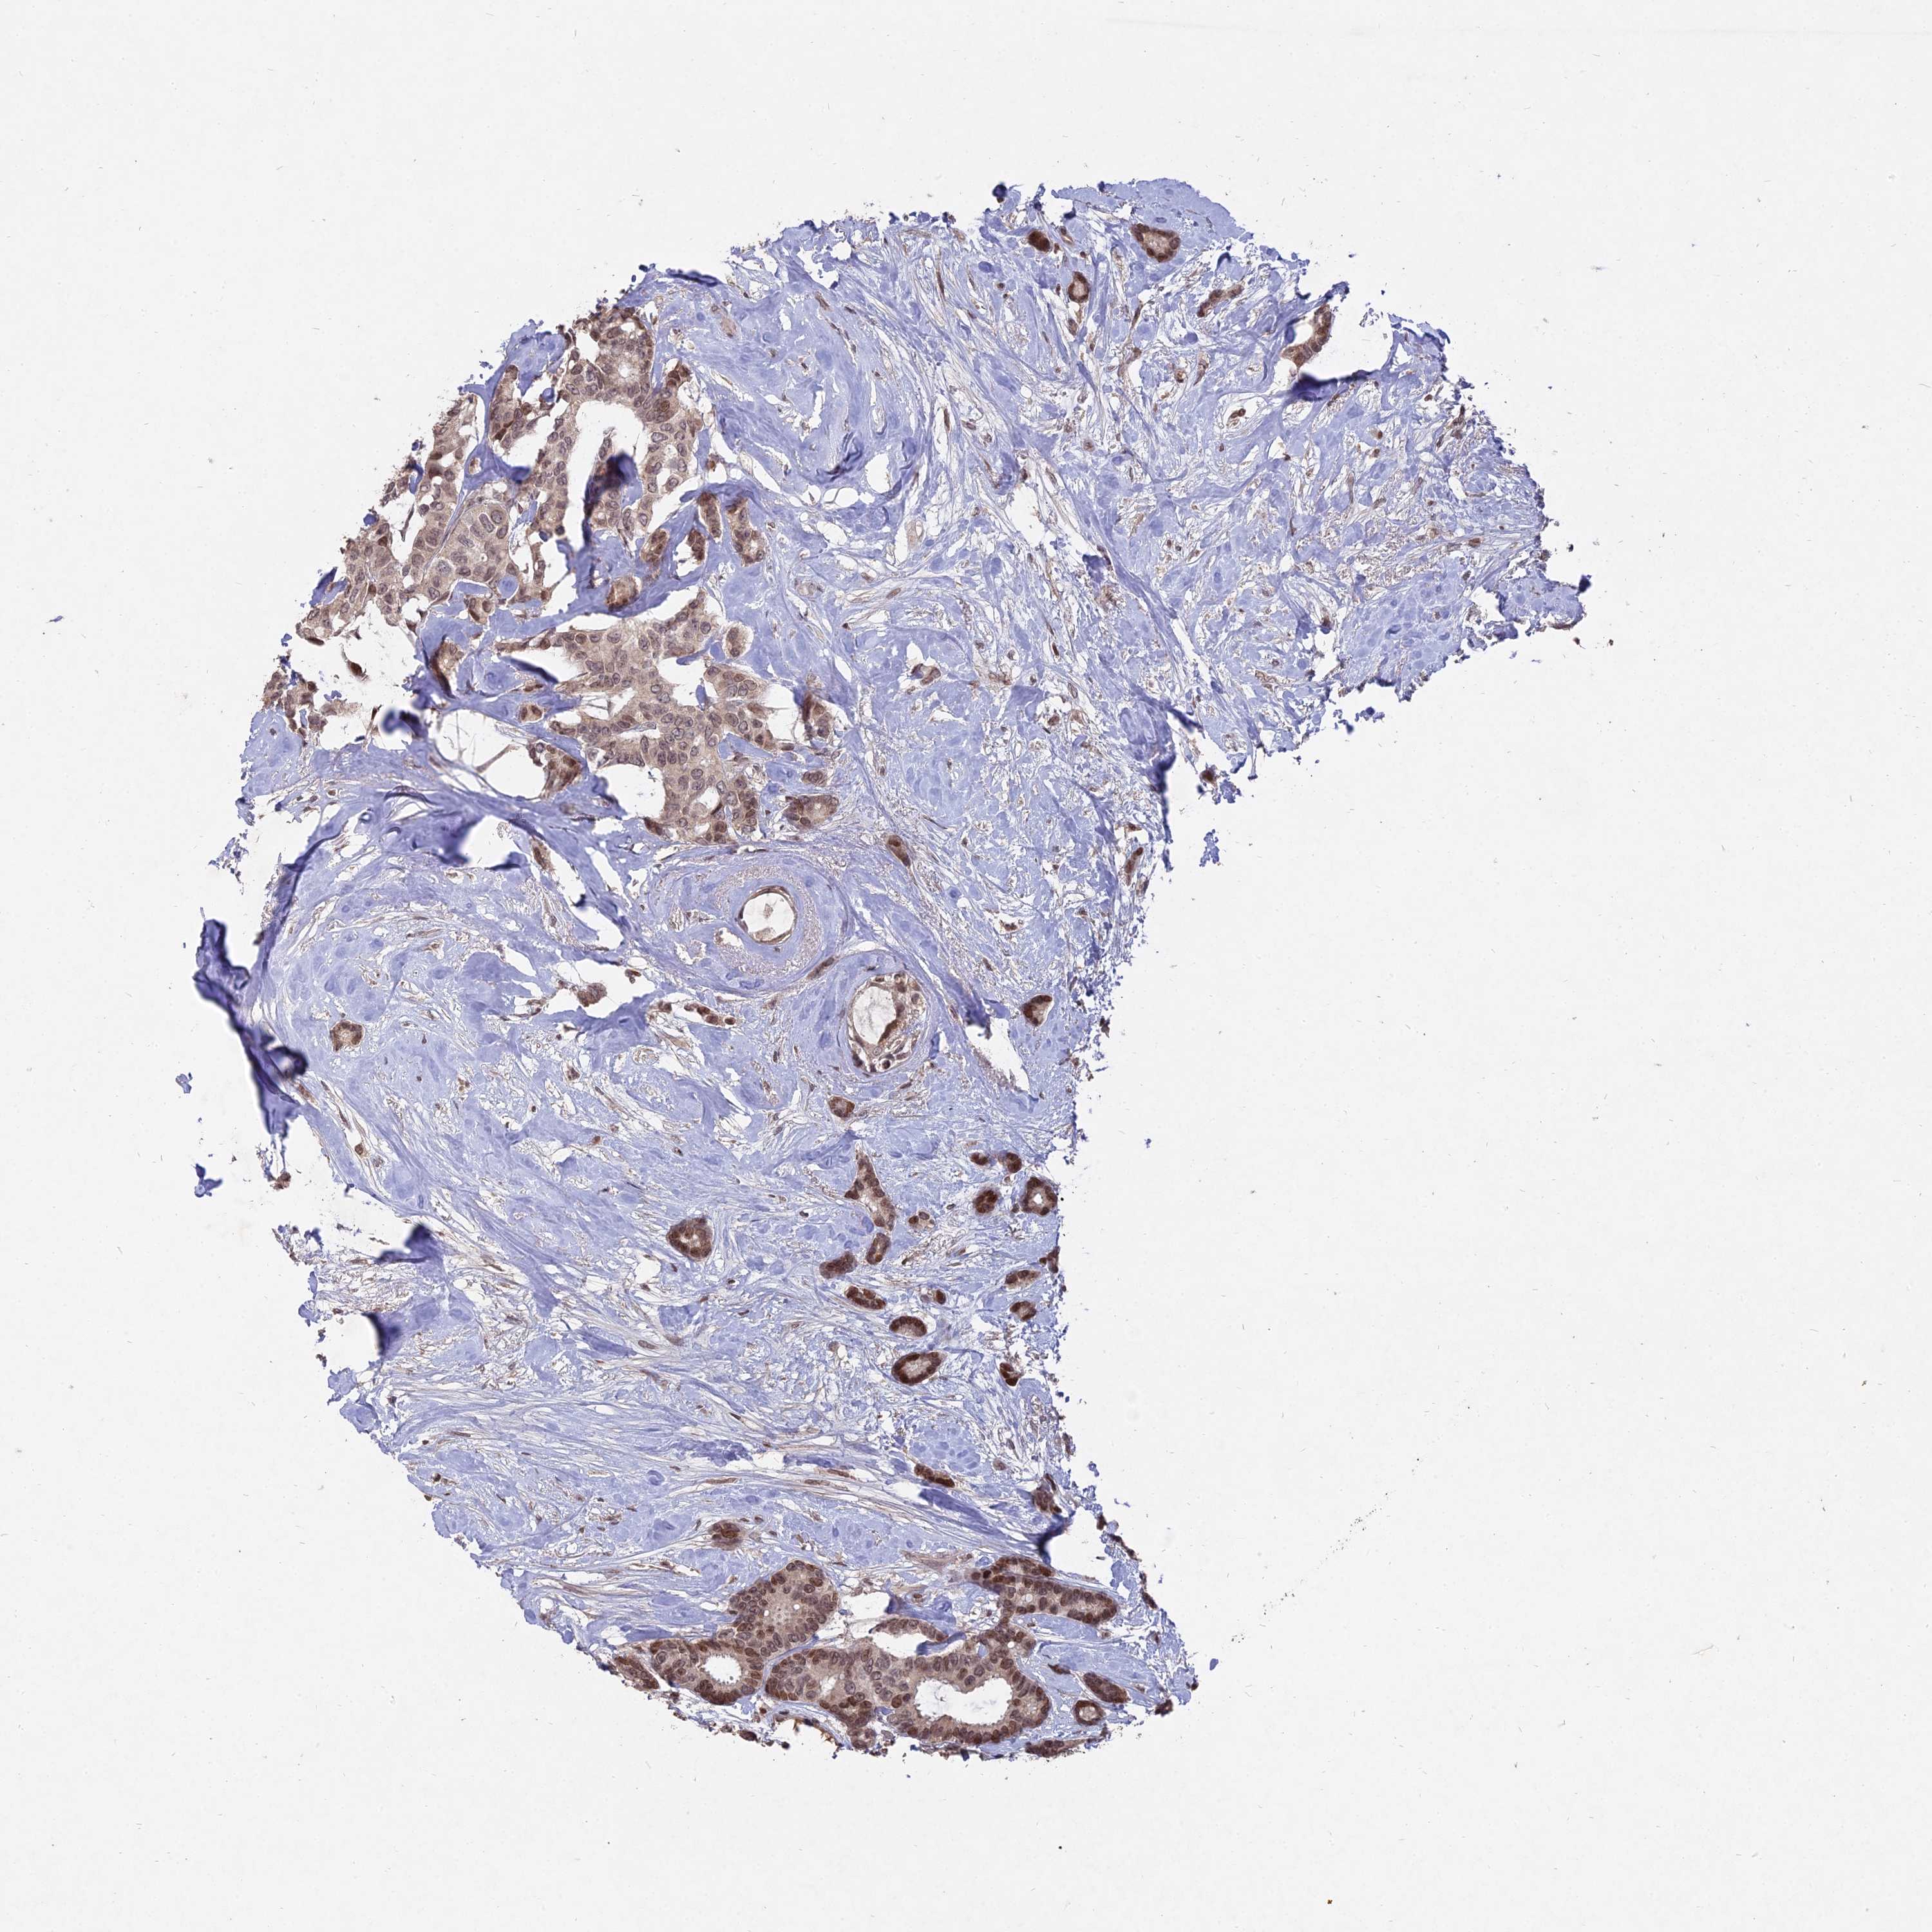

CANCER BREAST CANCER Show tissue menu

BRCA TCGA BRCA VALIDATION PROTEIN EXPRESSION